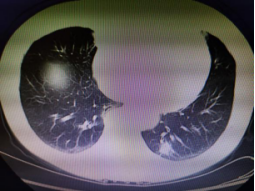

近日,一位高齡患者因體檢發現左下肺占位,前往我院胸心外科就診。在完善相關檢查后,評估為肺惡性腫瘤可能性極大,必須及時切除。為最大限度減少手術產生的不良反應,艾成決定為患者實施創傷小、術后疼痛輕、恢復快的單孔胸腔鏡下肺癌根治術。

術中先行肺占位楔形切除,冰凍活檢證實為“腺癌”,遂進一步實施肺葉切除+系統淋巴結清掃術,兩小時左右,手術順利完成,術中出血不到50ml,手術切口僅3cm,患者恢復良好。

CT提示左下肺占位直徑約20mm 手術中 單孔微創切口